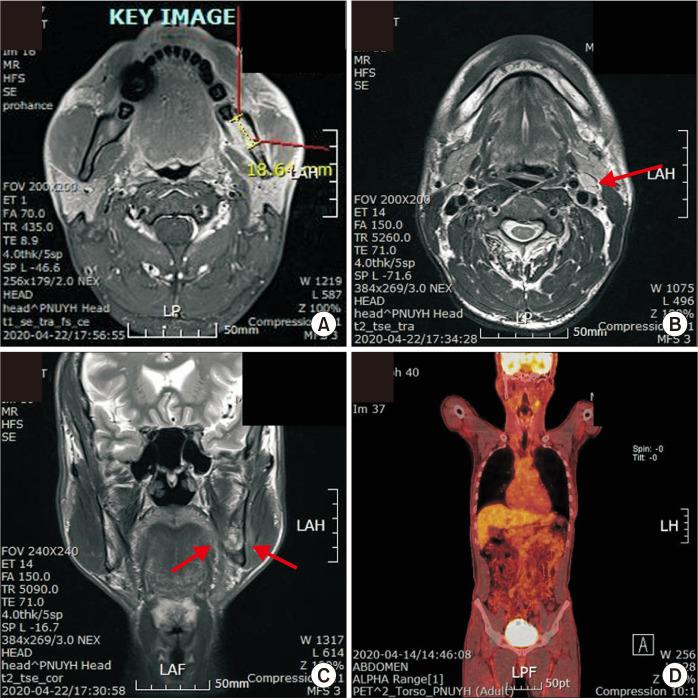

Primary intraosseous squamous cell carcinoma (PIOSCC) is very rare type of squamous cell carcinoma (SCC) that occurs within the jaw and arises from remnants of odontogenic epithelium with no connection to the oral mucosa. This study reports two cases of PIOSCC of the mandible. Reported in this article are two cases of PIOSCC of the mandible that were treated with resection and reconstruction using a fibular free flap. The first case was a 36-year-old male patient who complained of right mandibular pain. Computed tomography (CT) and panoramic radiograph revealed a large radiolucency in the mandibular ramus area. At first, an odontogenic keratocyst was tentatively diagnosed, and an excision procedure was carried out at another clinic. A final biopsy after cyst enucleation revealed well-differentiated SCC, so we proceeded with segmental mandibulectomy and reconstruction using a fibular free flap. The second case was a 48-year-old male patient with left mandibular pain. CT and panoramic radiograph revealed irregular radiolucency in the mandibular angle area near tooth #38. At first, osteomyelitis was tentatively diagnosed, and a curettage was carried out. A later biopsy revealed well-differentiated SCC, so segmental mandibulectomy and reconstruction with a fibular free flap were secondarily performed. Our two cases have had no recurrence. The facial appearance of both patients is satisfactory, and the neo-mandibular body created using a fibular bone transfer displays adequate bony volume.

原发性骨内鳞状细胞癌(PIOSCC)是一种非常罕见的鳞状细胞癌(SCC),发生于颌骨内,起源于牙源性上皮残余,与口腔黏膜无连接。本研究报告了两例下颌骨PIOSCC病例。本文报道了两例下颌骨PIOSCC病例,采用游离腓骨瓣进行切除和重建治疗。第一例是一名36岁男性患者,主诉右下颌疼痛。计算机断层扫描(CT)和全景X线片显示下颌支区域有一个大的透射区。起初,初步诊断为牙源性角化囊肿,并在另一家诊所进行了切除手术。囊肿摘除后的最终活检显示为高分化SCC,因此我们进行了下颌骨节段性切除并用游离腓骨瓣进行重建。第二例是一名48岁男性患者,有左下颌疼痛。CT和全景X线片显示38号牙附近下颌角区域有不规则透射区。起初,初步诊断为骨髓炎,并进行了刮除术。后来的活检显示为高分化SCC,因此二期进行了下颌骨节段性切除并用游离腓骨瓣进行重建。我们的两例病例均无复发。两名患者的面部外观均令人满意,使用腓骨骨移植构建的新下颌体显示出足够的骨量。